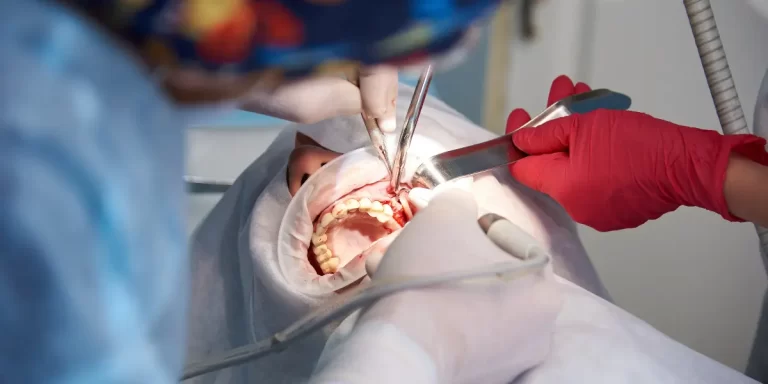

Descubra tudo sobre a cirurgia de enxerto ósseo dentário, procedimento pioneiro no Brasil que ajuda a...

Na minha prática profissional, gosto de me manter sempre atualizado e compartilhar com os meus pacientes...

Ao longo da minha trajetória profissional, muitos dos meus pacientes ainda se assustam ao ouvir falar...